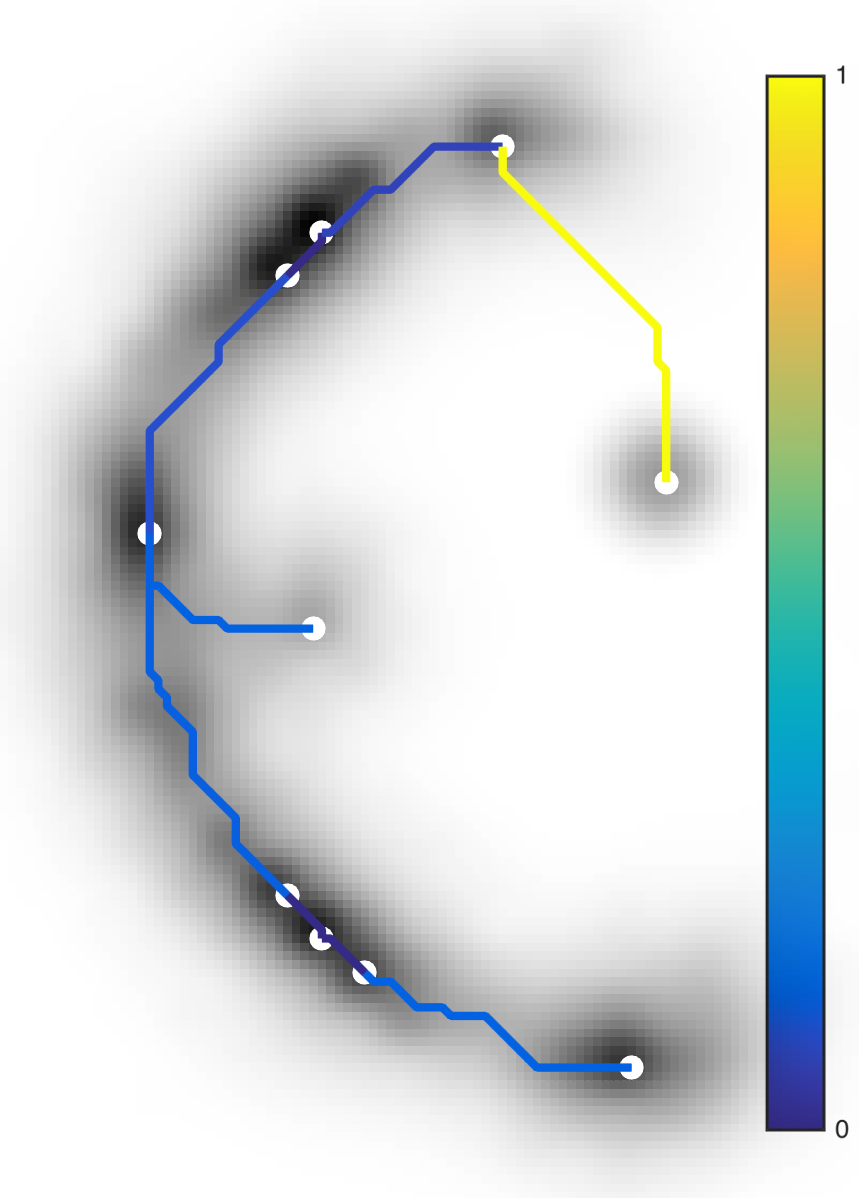

2.2 Vascular Tree of Geodesic Minimal Paths

Following the concepts first introduced in [4], we formulate an anisotropic front propagation algorithm that combined with an acyclic connectivity paradigm joins multiple sources propagating concurrently on a Riemannian speed potential . Since we want to extract geodesic minimal paths between points, we minimize an energy functional for any possible path between two generic points along its geodesic length, so that , and . The solution to the Eikonal partial differential equation is given here by the anisotropic Fast Marching (aFM) algorithm [4], where front waves propagate from on , with describing the infinitesimal distance along , relative to the anisotropic tensor . In our case, , and . Note that the anisotropic propagation is a generalised version of the isotropic propagation medium, . The acyclic connectivity paradigm is run until convergence together with the aFM to extract the vascular tree of multiple connected geodesics .

Geodesic paths are determined by back-tracing when different regions collide. The connecting geodesic is extracted minimizing at the collision grid-points. The aFM maps, i.e. ; the Voronoi index map , representing the label associated to each propagating seed; and the Tag , representing the state of each grid-point (Front, Visited, Far), are then updated within the collided regions, so that these merge as one and the front is consistent with the unified resulting region. This is continued until all regions merge.

Initialization. The seeds are aligned towards the vessels’ mid-line with a constrained gradient descent, resulting in an initial set of sources . All 26-connected components initialize the aFM maps, i.e., , , , and constitute also the initial geodesics .

Fast Marching Step. The aFM maps are updated by following an informative propagation scheme. We refer to [4] for the 3D aFM step considering the 48 simplexes in the 26-neighbourhood of the Front grid-point with minimal .

Path Extraction. Collision is detected when Visited grid-points of different regions are adjacent. A connecting is determined by linking the back-traced minimal paths from the collision grid-points to their respective sources with a gradient descent on (fig. 2). The associated integral geodesic length is computed and the connectivity in is updated in the form of an adjacency list. Lastly, the grid-points of the extracted are further considered as path seeds in the updating scheme, since furcations can occur at any level of the connecting minimal paths.

Fast Updating Scheme. A nested aFM is run only in the union of the collided regions using a temporary independent layer of aFM maps, where , , and . Ideally, the nested aFM is run until complete domain exploration, however, to speed up the process, the propagation domain is divided into the solved and unsolved sub-regions, and the update is focused on the latter (fig. 2). The boundary geodesic values of equal the geodesic distances at the collision grid-points. Lastly, the aFM maps are updated as: , , and .